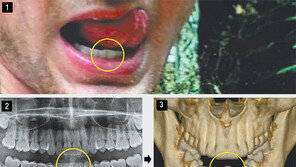

북한을 방문했다가 혼수상태로 풀려난 뒤 사망한 미국 대학생 오토 웜비어가 북한에 있을 때 고문을 당했을 가능성이 있어 보인다는 의사 소견이 나왔다. 그동안 북한은 ‘(웜비어가) 보툴리누스균에 의한 식중독에 걸려 치료 과정에서 수면제를 복용하고 혼수상태에 빠졌다’고 주장해 왔다. 2…